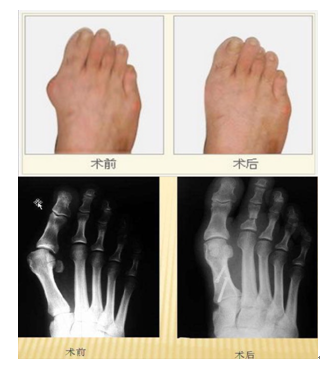

说起“踇外翻”,也许许多人会感到陌生,但一提到它的俗名“大脚骨”大家就很熟悉了,踇外翻的形成多与遗传(约占 80% 以上),穿鞋不适有关。好发于女性朋友(男女比例约 1 : 30 )的一种常见足部畸形,多呈对称性。它的主要表现就是:足踇趾斜向外侧,第一跖骨内翻,第一二跖骨间夹角增大,跖踇关节轻度半脱位;第一跖骨头在足内侧形成一骨赘,因长期受鞋帮的摩擦,局部皮肤增厚,严重时红肿发炎,即形成我们所说的踇囊炎。踇外翻严重时,第二趾可被踇趾挤向背侧,形成锤状指。踇外翻作为一种疾病,随着年龄增长,畸形程度会加重,会产生很多严重的并发症,如踇囊炎、爪形趾、鸡眼、脚垫等;这些并发症的发生不仅影响足部功能,而且会产生疼痛,严重影响生活和工作。

对于中晚期病人,若要彻底治愈,只有采用手术治疗,手足踝显微外科为大家提供以下几种常见有效的手术方法,包括:①软组织手术:主要将踇收肌在近节趾骨的止点切断,移位于第1趾骨头的腓侧,以McBride(软组织松解术)手术为代表②骨切除术:切除部分骨骼,使挛缩的软组织松弛以解除症状,常见手术为Mayo和Keller术③第1跖趾关节融合术④小切口手术⑤矫正第1跖骨内翻截骨术,或同时实施软组织手术和(或)骨切除术。